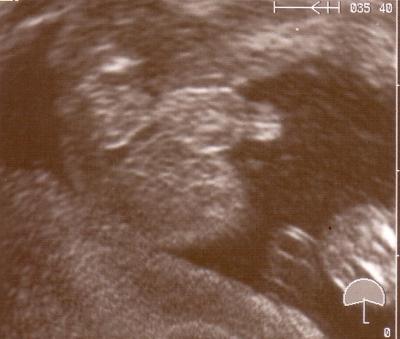

...ratet mal?!

Kann diese Bilder nicht gut erkennen, aber dieses ist eindeutig!!!! wie schön!!!!

soweit ich das erkennen kann, hängt doch da was dazwischen, oder?? Zumindest sieht es anders aus, als bei unserem Mädchen-Outing! Glückwunsch!!!

Na, das sieht doch ziemlich nach nem Jungen aus! Glückwunsch!

also ich würde auch behaupten es ist ein junge :D herzlichen glückwunsch zu dem kleinem

Na wenn das mal kein kleiner Stammhalter ist Na dann herzlichen Glückwunsch!!!

ich bin eindeutig(st) ein Junge :-) Herzlichen Glückwunsch